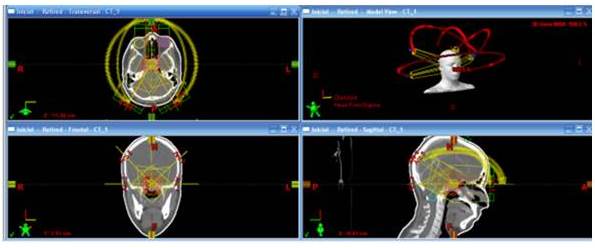

SISTEMA NERVIOSO CENTRAL

En estos casos la técnica RAVM ofrece mayor ventaja cuando la lesión se encuentre cerca de estructuras a riesgo cuyas tolerancias son mucho menores a la dosis final a impartir (quiasma, nervios ópticos, globo ocular, cócleas, etc.). Se usan arcos con Rayos X de 6 MV y el paciente se posiciona decúbito supino. La disposición de estos arcos no es estándar, por lo que el número de estos, ángulo de inicio y finalización del arco y ángulo de la camilla dependerá intrínsecamente de la ubicación de la lesión, tamaño de esta y disposición de las estructuras a riesgo. Para este tipo de planes el tratamiento dura de 3 a 5 min lo cual es menor al tiempo que toma si se emplea RTIM el cual seria de alrededor de 10 min.

En la Figura 6 se muestra la distribución de dosis en plano axial, coronal y sagital del plan de un tratamiento de un macro-adenoma hipofisario, además de una vista tridimensional de la disposición de los arcos.